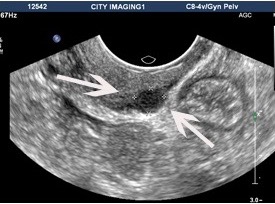

The larger the lesion, the easier it is to see on ultrasound, but in the hands of experienced imaging specialists lesions of only a few millimetres may be diagnosed. Endometriosis lesions on ultrasound look darker (seen as blacker) on ultrasound.

The left image shows a small lesion on the back of the vagina, causing pain with sexual intercourse. The right image shows a large bowel lesion, which seems very easy to see, but unless the bowel is inspected, it is not noticed on routine pelvic ultrasound.